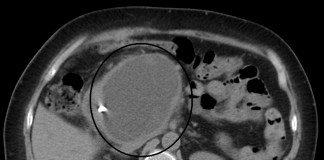

Chistul pancreatic – Cum apare si ce simptome creeaza in organism

Pancreasul face parte din categoria organelor sistemului digestiv si este cea mai vulnerabila parte a acestuia. Se afla situat sub stomac si are forma...